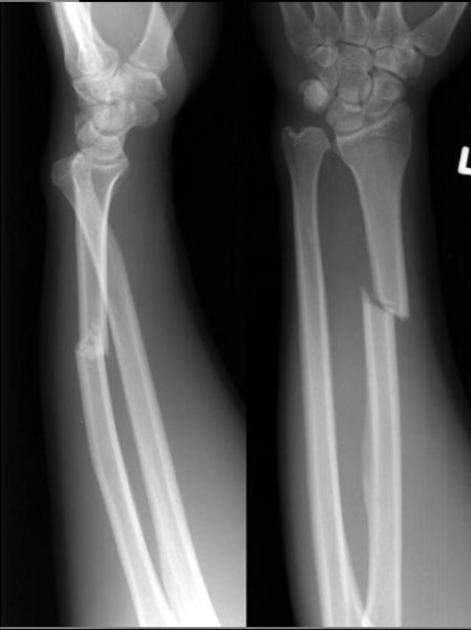

Diagnosis?

Galeazzi fracture/dislocation. Due to fall on outstretched hand with pronated forearm. Distal radial diaphysis fracture, ulnar dislocation at DRUJ (typically dorsal).

Risk of fracture nonunion, entrapment of the extensor carpi ulnaris tendon.